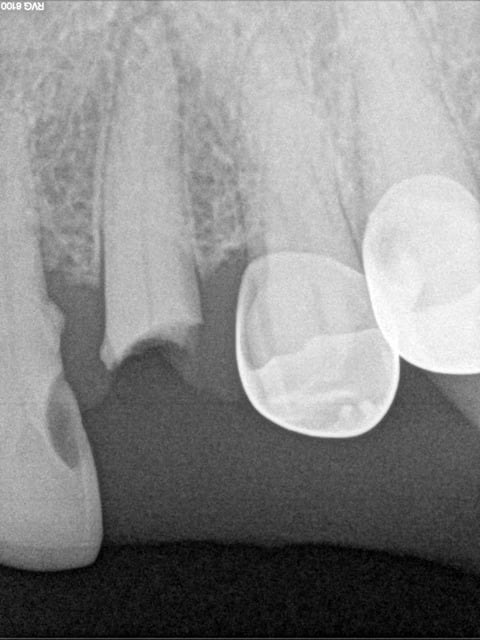

Il y a quelques temps un sujet avait mis le feu à la poudre d'oxyde de zinc .... Hodina s'était retrouvé avec une dent d'un patient dans la main et avait eu l'idée (saugrenue?)de la remettre...Il avait exprimé ses doutes dans le sujet : "1 ére fois que ça m'arrive" . S'en était suivi un débat passionné et passionnant où un certain Enlaye avait défrayé la chronique en exposant ses cas d'extractions / réimplantations ... (ERI !! ça le fait Enlaye) . Certains et même les plus nombreux avaient crié au fou !!! D'autres , dont moi , avaient prêté l'oreille , demandé des éclaircissements ... Bref , depuis Enlaye a gagné le respect des chantres de ce forum , il y apporte son humour , sa connaissance et son regard toujours intéressant ou drôle ,bref ,je suis fan ! (et ne chope pas la grosse tête , il y en a assez comme ça ici ! ) Cette idée d'extraction / réimplnatation me trottait dans la tête ...fallait que j'essaye : pas besoin de matos sophistiqué , pas besoin de formation ... fallait trouver le cas . Donc mi Novembre , une patiente de 71 ans se pointe avec une 23 cassée , sous gingival , à peine visible : la gencive ayant presque recouvert tout ça . Un stellite étant à dispo , je me dis : j'extrais et hop une adjonction .... Je prends une radio , la racine est belle .... Entre les 2 rendez vous , je cogite : et si ..... La fois suivante , je suis décidée , je vais tenter l'ERI , mon idée était de faire une "élongation coronaire" .... bref ..je vous passe les détails ... J'ai été enchantée du résultat !!! cela fait une semaine qu'elle a sa couronne définitive , sur une dent absolument pas mobile . Tout s'est super bien passé , aucune douleur (mis sous ATB) , certains diront que je suis allée un peu vite , mais bon , une provisoire c'est pas le top non plus . Alors , la conclusion de tout ça : j'y ai pris beaucoup de plaisir à tenter l'expérience , je ne dis pas que je recommencerais ça tous les jours ou même tous les mois. Je n'ai pas de recul sur cette dent , d'ici 6 mois , un an on verra ce que ça donne mais je ne pensais vraiment pas que cela soit possible alors je remercie Enlaye pour cette ouverture de mon petit esprit sclérosé , et je vous invite à tenter l'expérience .

Ha , ha , ha je savais que tu visais plus bas !! Bon je vais faire vite : alors endo in situ , sans digue ( waouh , mais t'es di(n)gue là ! remarque je me demande bien ou je l'aurais accroché le crampon , aux oreilles peut-être ?, alors plein de sales bébêtes sont passées par là , j'me demande même si j'étais pas enrhumée ce jour là .. ça c'est pour Ameli !!! ) . La fois suivante , je réalise une provisoire mais le hic c'est que le logement de tenon ,ben j'arrivais pas à avoir une longueur satisfaisante , ça butait sur les dents adjacentes .... Prov en tab 2000 et moule ... Puis vient le grand jour de l'extraction réimplantation : je vire manteau , sac , chaussures ..... hi hi hi .. bon rien en fait ! Je m'arme d'un bon petit davier et la dent, sympa comme la patiente, vient facilement ! Et là tout devient plus facile , je refais mon logement de tenon à la bonne longueur (trop facile!) et j'ajuste ma provisoire aux petits oignons ... surtout en distal et mésial bien sûr . Et je remets gentiment tout ça en place . Pb , ça ballote dans tous les sens ! ouille ouille , mal barré mon affaire ! J'avais prévu une contention avec une grille et du compo fluide : pb le compo sur de la résine ça tient pas bien ! et la dent se balade quand même un peu . je m'y reprends à 2 ou trois fois avant que j'obtienne un truc qui tienne.Bon faut pas y aller franco non plus . Ce qui m'a aidé ( et a aussi facilité ma décision) c'est qu'en antagoniste , il y avait une PAP .. donc une certaine souplesse !!!Le hic , c'est que pour l'élongation coronaire ben c'est pas ça , la coquine est retournée bien sagement dans son cocon . Bon bon bon , on verra . La patiente est cool , et prévenue qu'il va pas falloir croquer des smarties de ce coté là , je la mets sous ATB et roule ma poule ! J'attends la semaine suivante avec curiosité mais une pointe d’anxiété quand même : a t-elle expulsé sa valda en éternuant ? s'est elle tordue de douleur ? la contention a t'elle tenu ? Et la semaine suivante : tout va bien : pas de douleur , la dent et sa provisoire sont là . Tuti va bene ! Rendez-vous 5 semaines plus tard : faut que j'en ai le cœur net : je dépose ma contention qui ne résiste vraiment pas beaucoup ! je teste la mobilité : nada , rien ! tout va bien . La gencive est impeccable,un miracle ! le jonction gencive , dent est bien nette : que demande le peuple ! La suite est classique . Voili , voilà ;

Après je suis peut être parano avec ces histoires de retro alvéolaire mais il n'y a pas un truc à l'apex quand même, le cone beam le confirmerait ... ou pas ;)